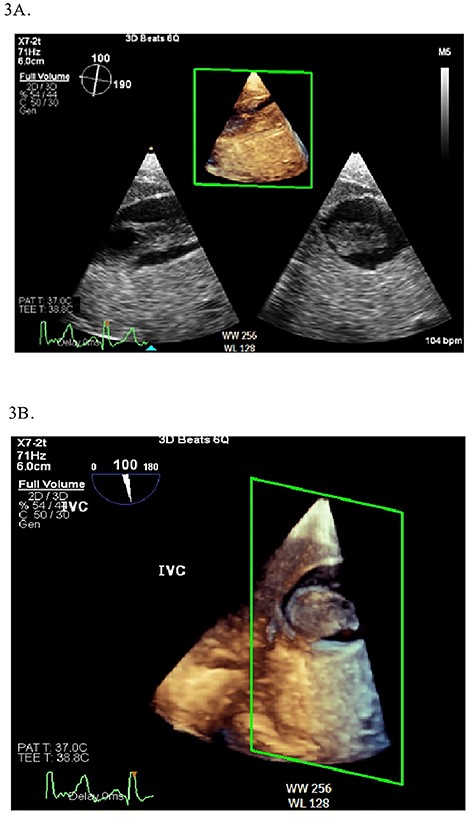

Continuous intraoperative transesophageal echocardiography (TEE) was performed. Postinduction TEE showed a large mobile mass of heterogeneous echogenicity in the RA abutting the tricuspid valve, mild tricuspid insufficiency, occlusive thrombus in the IVC and LV ejection fraction of 40% (Figs 2 and 3; Supplementary Materials S1 and S2). Given the location, size and mobility of the mass in the RA, the decision was made to remove it on CPB to minimize the risk of large embolus and significant blood loss. During the prebypass period, following laparotomy and drainage of abdominal ascites, the patient required significant colloid repletion with 5% albumin and blood products for hypotension, underfilled LV on TEE and low central venous pressure.

2D (A) and 3D (B) illustration of the IVC thrombus in long and short-axis views.